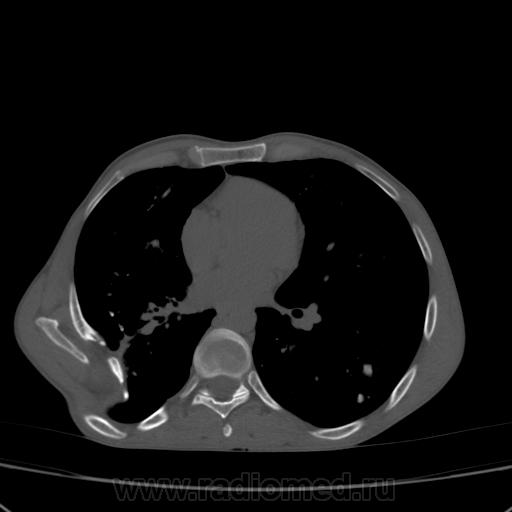

Состояние после торакопластики.

Молодой человек 30 лет, в 04 году выявлен фиброзно-кавернозный ТБ, в течение 12 месяцев лечился в стационаре, прооперирован-5реберная торакопластика справа, через 3 года переведен в 3ГДУ, в 10году снят с ДУ по излечению. Пришел провериться по ухудшению состояния. На КТ легких данных за рецидив ТБ, вроде нет. С " торакопластикой" был единственным пациентом на учете.

Состояние после правосторонней 5-реберной торакопластики по поводу ФКТ.Грубые остаточные изменения:поликистоз,буллезно-дистрофические изменения,плевропневмоцирроз правого легкого..Нет ли  мелкоочаговой диссеминации в обоих легких?Нужен Rархив.(ПТД).